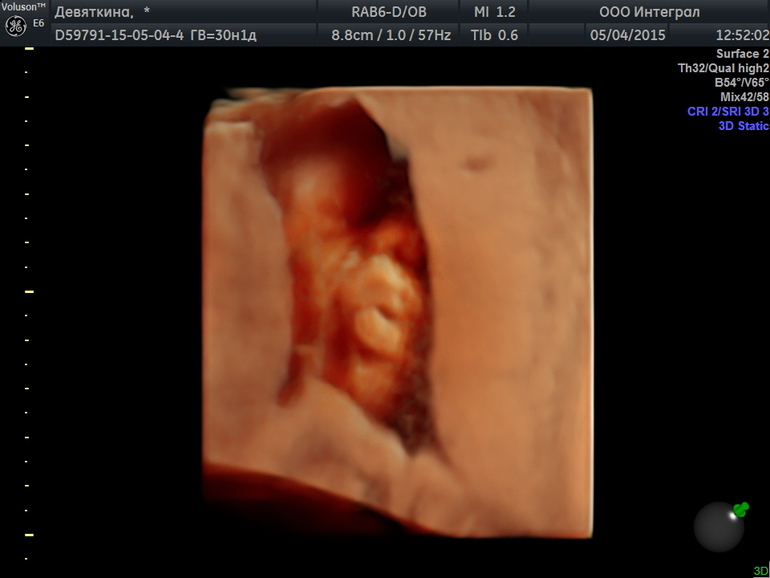

Целовательные фоточки Даниилушке!

Такие губки целовательные

Губки бантиком!